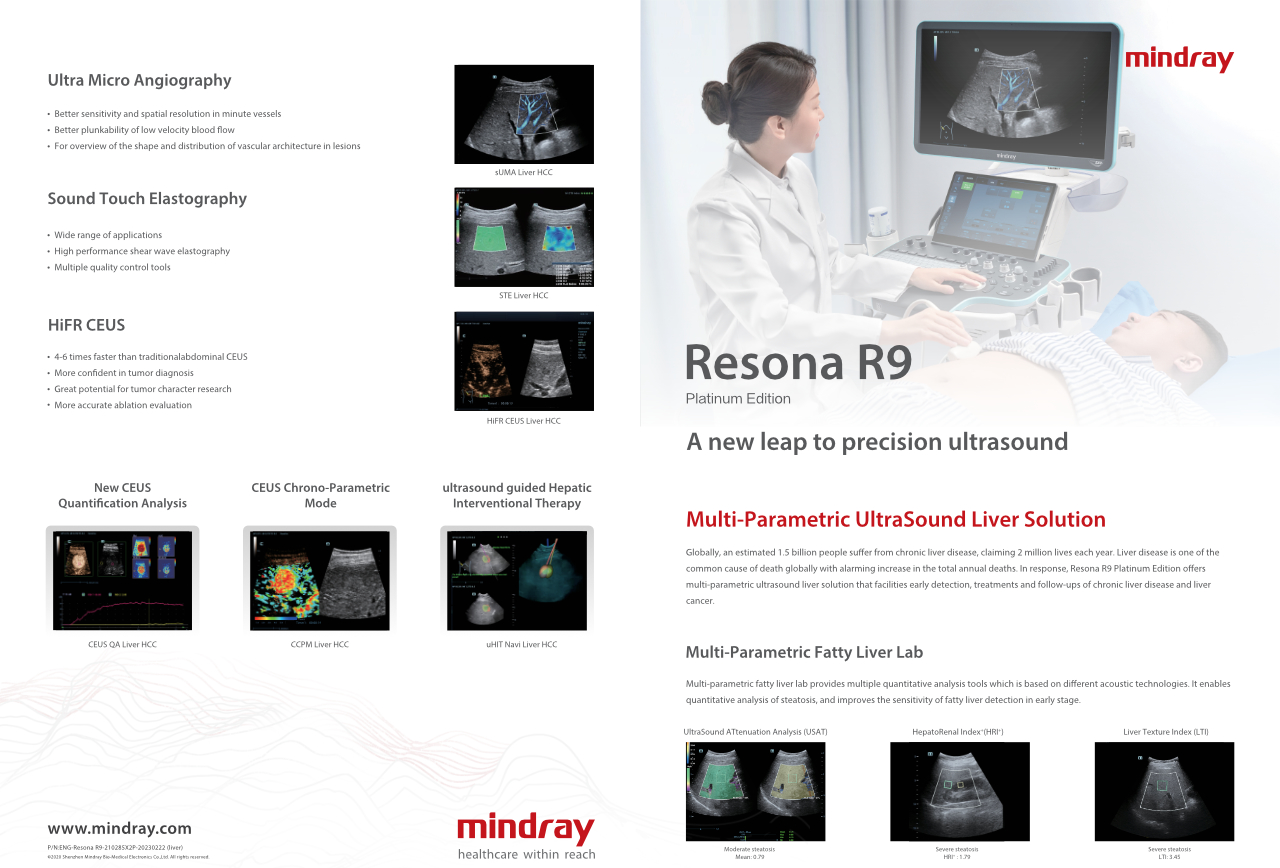

Jak wyra?nie mo?na zobaczy? w?trob??

W przypadku ogniskowych zmian w w?trobie, takich jak naczyniaki czy nowotw├│r w?troby, obrazowanie USG z kontrastem odgrywa wa?n? rol?. Technologia obrazowania USG z kontrastem UWN+ mo?e pom├│c uzyska? lepsz? penetracj?, lepsz? jako?? obrazu z ni?szym indeksem mechanicznym MI oraz d?u?szy obserwowany czas perfuzji.